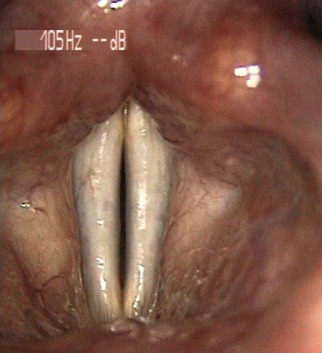

2594. Данная ларингеальная картина характеризует дисфонию